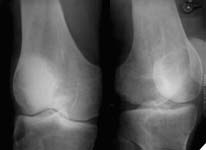

At the present time a post traumatic defect of lateral femoral condyle is observed. On the X-rays of left knee, a lateral femoral condyle defect is observed up to the 1/3 of the joint surface. Clinical examination of left knee joint revealed moderate atrophy of the muscles of left femur and shin, moderate pain with palpation of the lateral joint line, pathological deviation of the shin to the outside up to 20 degrees at doing the clinical tests, accompanied by the appearance of moderate pain, motions in the knee joint are slightly restricted.